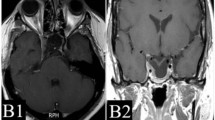

Example of hypofractionated SRT using CyberKnife for a patient with growth hormone-secreting pituitary adenoma. a Gadolinium-enhanced coronal MRI before SRT and the visual field test. b CyberKnife planning. c Gadolinium-enhanced coronal MRI and the visual field test 11 months after SRT. d Gadolinium-enhanced coronal MRI 120 months after SRT

In the present study, there were many cases in which tumor shrinkage or complete response was observed after SRT when evaluated by diagnostic imaging; however, the effects observed on these images were not reflected in biochemical data. Figure 3 shows one such case. This was a 25-year-old woman with acromegaly who had visual field abnormalities after multiple surgeries and drug therapy, and was then judged to be inoperable. Before hypofractionated SRT, GH was 3.5 ng/ml and IGF-1 was 310 ng/ml. She underwent hypofractionated SRT using CyberKnife with 31.7 Gy in 5 fractions to her 12.4 cc tumor. Eleven months after hypofractionated SRT, the tumor achieved a partial response, and improvements were noted in the visual field. At 120 months, the tumor achieved a complete response when rated by diagnostic imaging. However, hormone levels failed to completely satisfy the Cortina consensus (GH 5.2 ng/ml, IGF-1 305 ng/ml). Thus, in the present study, there were many cases in which the control of a macroscopic tumor did not satisfy the Cortina consensus criteria. Even when tumor volumes are controllable by hypofractionated SRT, achieving the suppression of GH appears to be difficult with this therapy alone. Although the possibility that hormones are produced by another co-existing microscopic tumor cannot be ruled out, the satisfactory control of symptomatic GH-PA requires multidisciplinary treatments, involving a combination of surgery, drug therapy, and irradiation. Landolt et al. [36] reported that patients in whom drug therapies were stopped before SRS had improved hormonal control than those who continued drug therapies. Although that was a small retrospective nonrandomized study, separating the two groups may be better considered in the future study. The conventional belief that complete endocrinological remission is achievable with radiotherapy alone needs to be reevaluated.